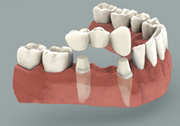

Tradional Crown and Bridge

Missing a tooth ? An Implant can replace that missing tooth in no time. Modern dental implants are precision devices, the most common type is a titanium screw that is anchored into the jawbone where it serves as post for a custom-made tooth crown. Once the crown is in place, you may not be able to tell it apart from your natural teeth.

Missing teeth and loose dentures make too many people sit on the sidelines and let life pass them by. However, today’s modern treatment plans can replace everything from a single missing tooth to a completely missing arch. Ask your dentist or dental specialist about the different dental implant options that are available to you. Don’t let another day go by without taking this important first step to restoring your confidence and your smile!